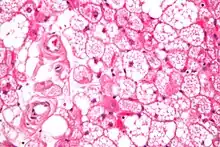

Hibernoma (intermediate magnification).

The tumors histologically resemble brown fat. There are four histologic types recognized, but one is the most frequently seen (typical). There is a background of rich vascularity.

- Lobular type: Variable degrees of differentiation of uniform, round to oval cells with granular eosinophilic cells with prominent borders, alternating with coarsely multivacuolated fat cells (pale cells). There are usually small centrally placed nuclei without pleomorphism. The cells have large cytoplasmic lipid droplets interspersed throughout.[3][4]